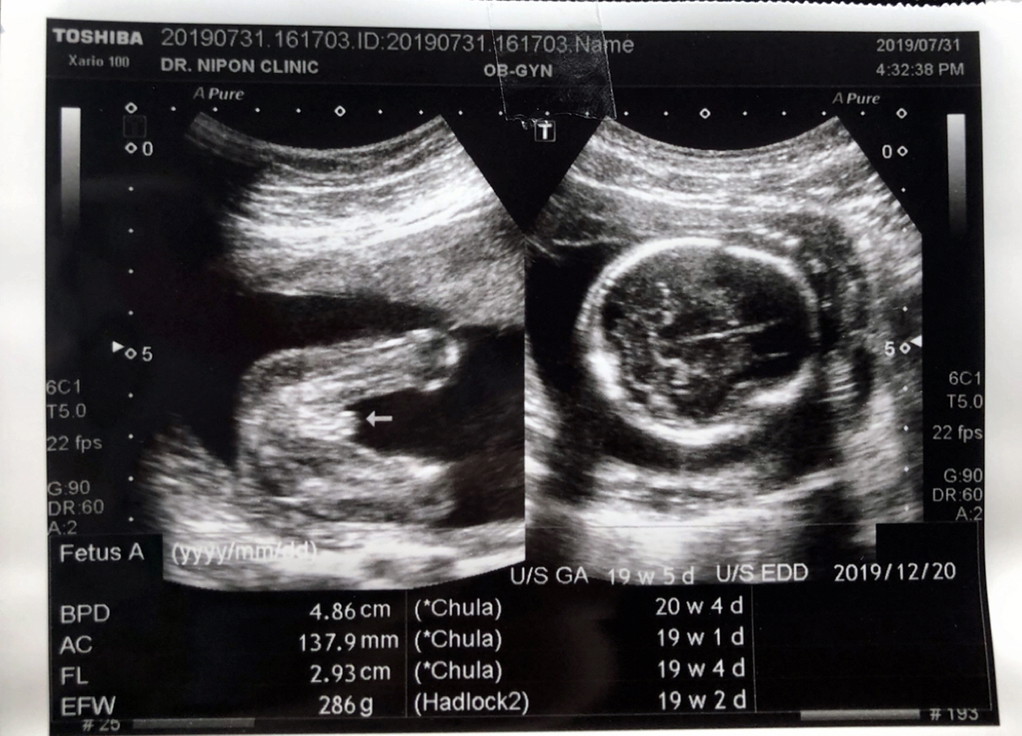

ซาวตอน4เดือนจะ5เดือนแล้วคะ

ตอนนี้5เดือนแล้วค่ะ